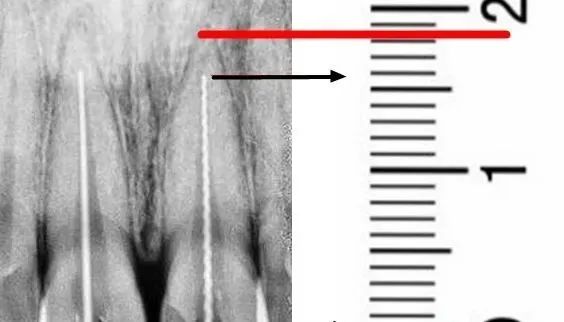

本著對病人負責的態度,我們將第一種方法定義爲耍流氓。電測法——根管測量儀,很多人認爲它是准確的,事實上,電測量仍然會受到很多限制和影響,首先,你如何測量嚴重出血的根管,根尖滲出物也會影響測量值,溶液的影響逐漸爲大家所知。然後我們需要引入另一種測量方法,X片檢查,通常這兩種方法結合在一起。![]()

事實上,無論插針是否插入根尖,其測量都是有意義的。插針片不像試尖片。你不必把它插到位。你只需要記住,k锉的工作刃是16毫米。按比例計算,上圖爲明顯示意圖,工作刃16毫米可計算出患牙的工作長度爲21毫米。即使你只插入一半,你也可以計算工作長度。是不是有很多朋友發現這幾年自己的插針片都白拍了?當然,X片也有缺點,因爲光線是平行投影的,所以彎曲、傾斜、側開和覆蓋都會導致測量誤差。

上圖是X片檢查誤差造成的情況。很多時候,它看起來不夠。事實上,它已經到了,但它看起來超過了。看起來超過了嗯哼,那就是超過了。所以有人說我們有CBCT,那我能說什麽呢?我們很高興在這裏談論火車和子彈頭列車。如果你和我們談論飛機,你很容易談論死亡。。。![]()